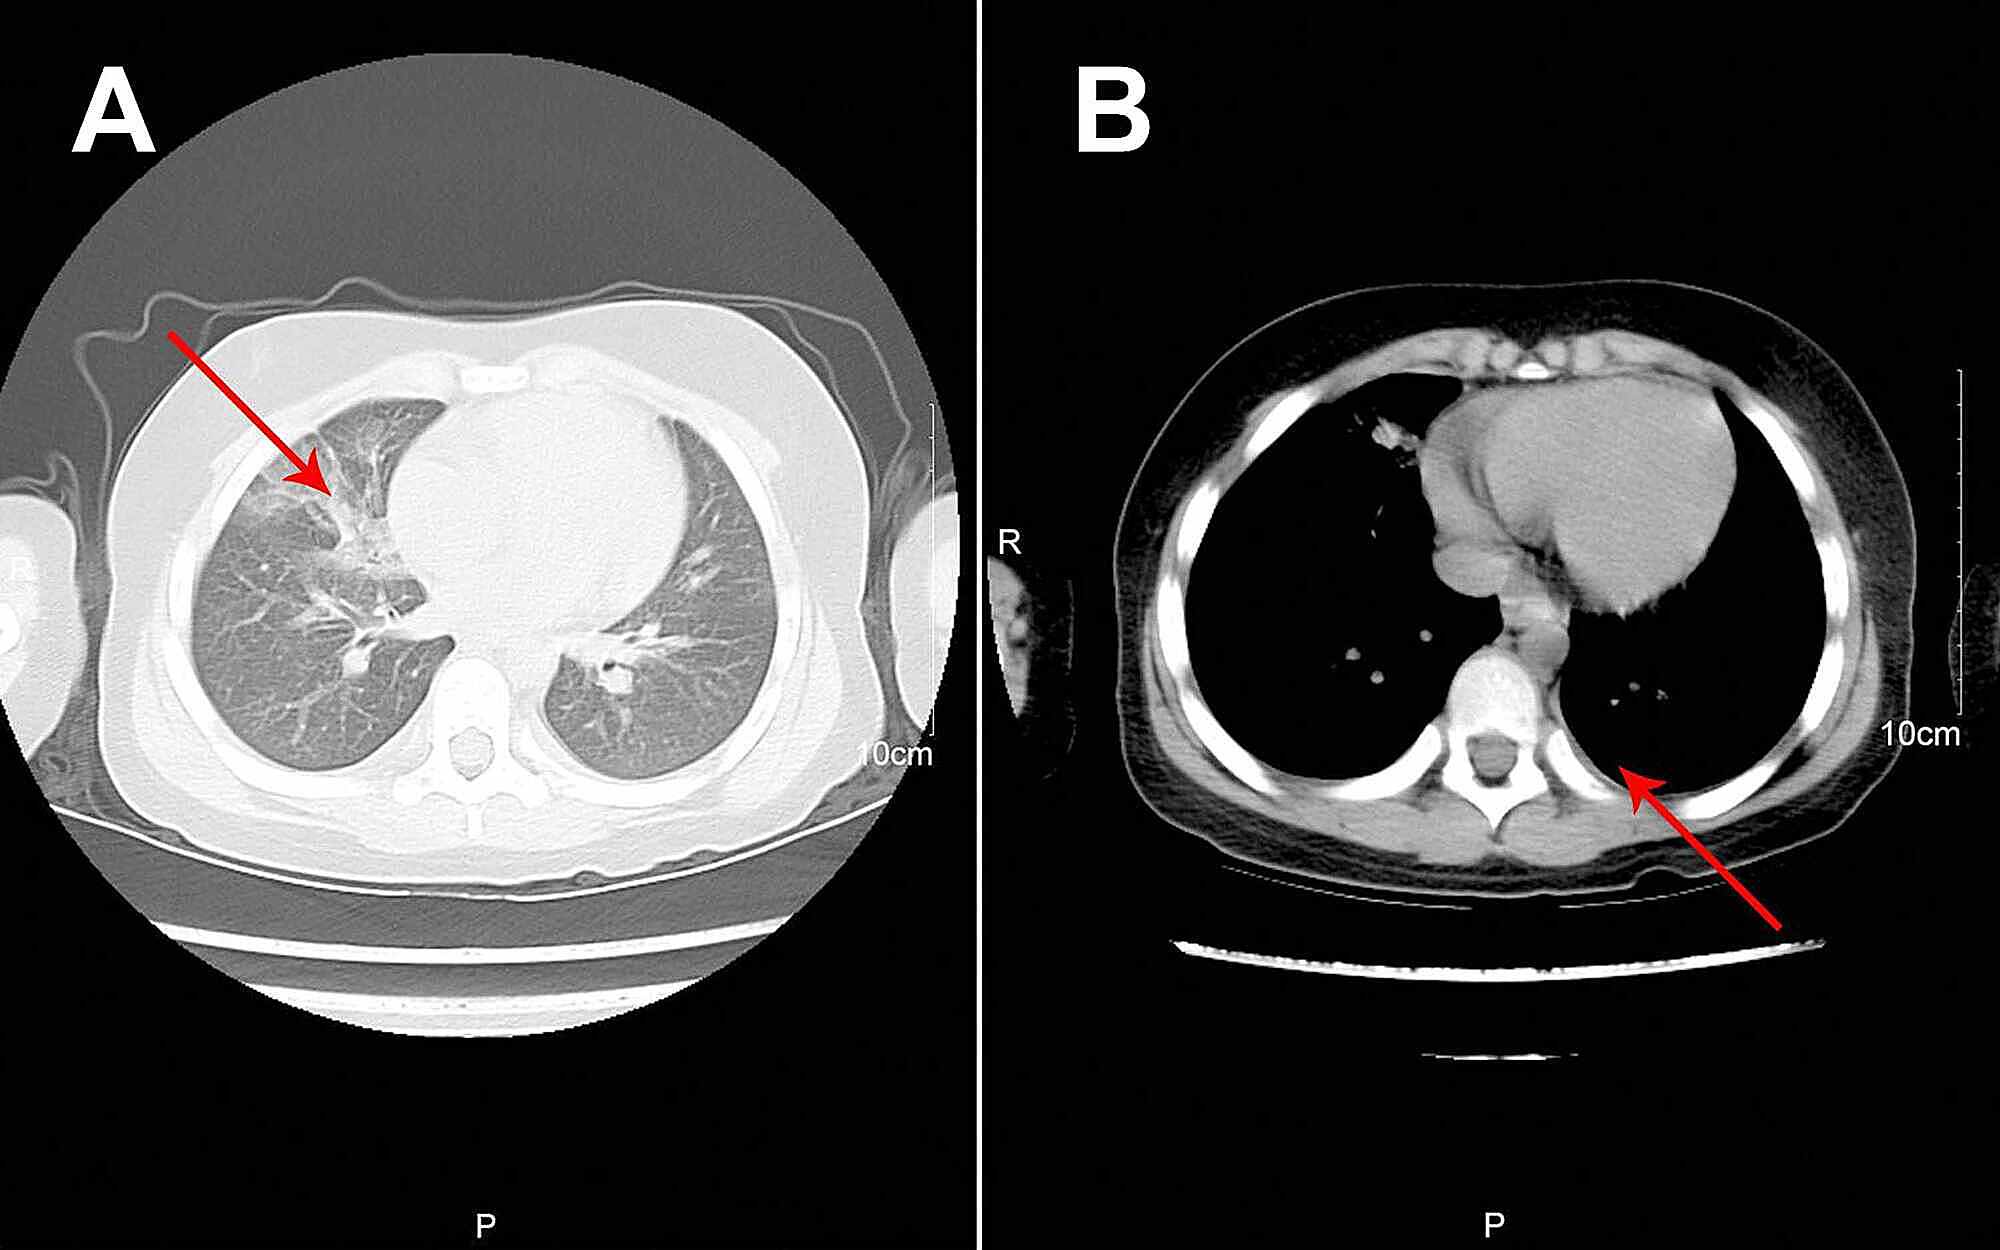

A previously healthy eight-year-old boy, without the history of wheezing and foreign body inhalation, was transferred to the emergency center of Jiangxi Provincial Children's Hospital from a basic-level hospital with a two-day history of fever, cough, and progressive dyspnea. His body temperature was approximately 38 °C. He had been previously treated with antibiotics at a local hospital without improvement except the normalized body temperature. Subsequently, he underwent chest computed tomography (CT) scans, which revealed atelectasis in the left lung and a foreign body in the left upper bronchus, along with pneumonia in the right lung (Figure 1A). In our emergency department, physical examination showed clouding of consciousness, cyanosis, rales, and diminished breath sounds in both lungs. Other parameters were as follows: body temperature, 36.9 °C; heart rate, 150 beats/minute; respiratory rate, 46 breaths/minutes; percutaneous oxygen saturation, approximately 70% under high-flow oxygen therapy. Since the local chest CT scan and clinical manifestations indicated a high possibility of foreign body inhalation, urgent bronchoscopy was performed. This procedure did not reveal the presence of any foreign body in the trachea of this patient but showed the presence of white gelatinous secretions that completely blocked the left main bronchus. Upon removal, it was observed that the secretions are shaped like a bronchial tree (Figure 2A). However, after this cast removal followed by bronchial lavage, there was no significant improvement in oxygen saturation, which fluctuated between 70% and 80%. The patient was admitted to the pediatric intensive care unit and intubated immediately.

After the observation of the cast that was removed via bronchoscopy, PB diagnosis was confirmed. Further, histopathology indicated that the casts predominantly comprised of inflammatory necrotic tissue, mucin, numerous neutrophils, and eosinophils (Figure 2C). Chest X-ray revealed pneumonia in both lung lobes and atelectasis in the left lung (Figure 1B), suggesting airway blockage by residual casts. Furthermore, complete blood count revealed the following: white blood cells, 13.11×109 cells/L (leukocytosis); neutrophils, 85.4%; hemoglobin, 145 g/L; and platelets, 350×1012/L. The blood biochemistry results of this patient were as follows: C-reactive protein (CRP), 42.6 mg/L; IgE, 908.4 IU/ml; IgA, 1.04 IU/ml; IgM, 0.62 IU/ml; and IgG, 12.15 IU/ml. As PB diagnosis is confirmed, along with extensive inflammatory necrotic tissue in the casts, we started treatments as follows: imipenem-cilastatin sodium (30 mg/kg, q6h) for anti-infection; azithromycin (10 mg/kg, qd); intravenous methylprednisolone (1 mg/kg, q12h); nebulized dexamethasone (5 mg, q6h) for anti-inflammation; nebulized bronchodilators, intensive chest physiotherapy, and intravenous mucosolvan for mucolytic therapy. However, oxygen saturation still fluctuated at approximately 80% without improvement for the next two days. Sputum etiology examination was positive for influenza A virus and negative for other viruses and Mycoplasma pneumoniae RNA, as well as fungi and bacteria. Additionally, blood cultures for bacteria and fungi were also negative.